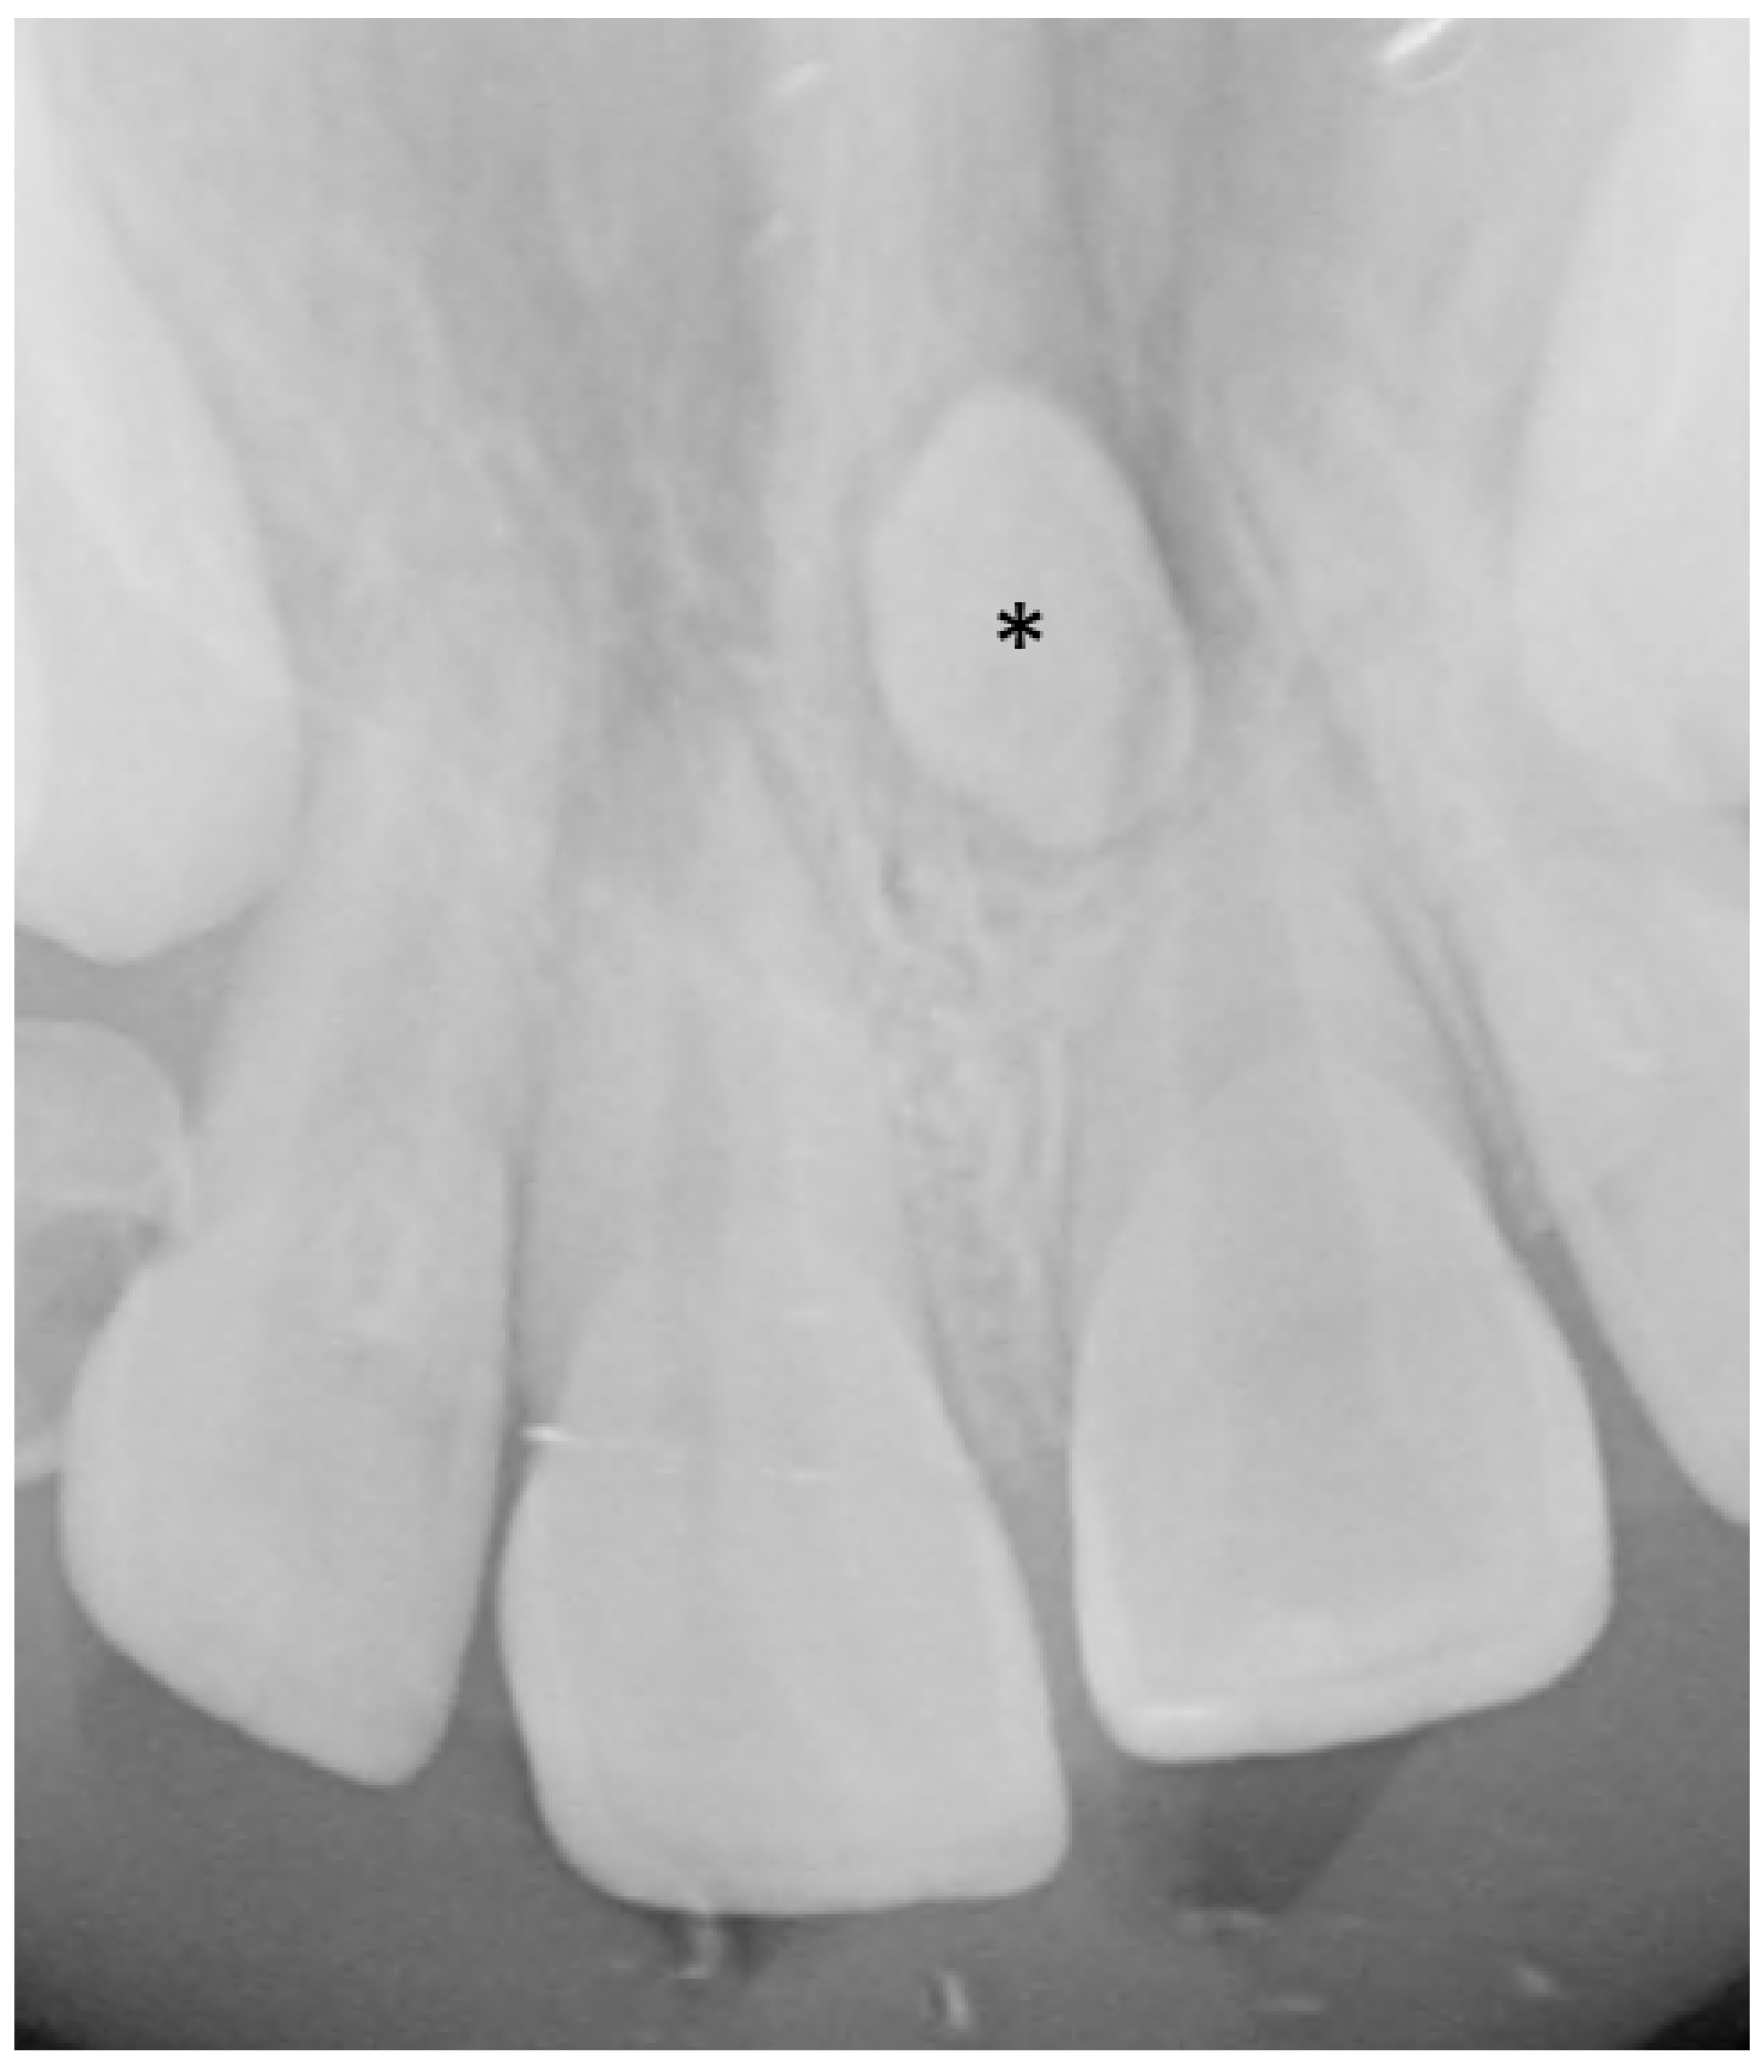

3.5.2. Dental Decay Radiologic Correlations